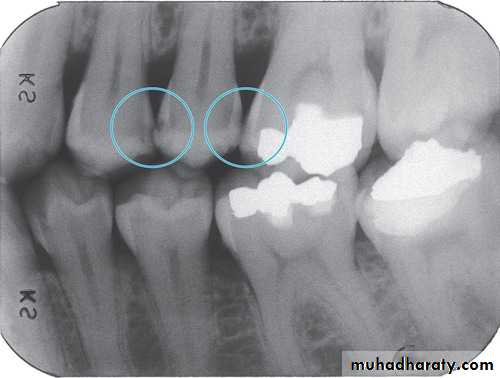

3. Radiography method

Types of X-ray radiograph images:• Periapical X-ray radiograph.

• Bitewing X-ray radiograph.

• Panoramic X-ray radiograph.